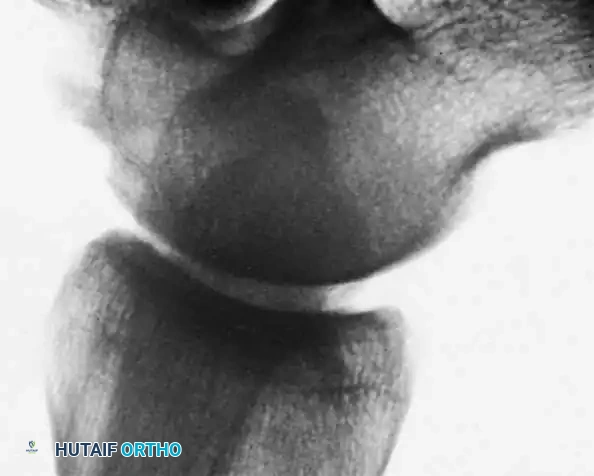

Fig. 13: MRI and corresponding arthroscopic view of a classic posteromedial osteochondral lesion of the talus.

Osteochondral Lesions of the Talus (OCD)

Osteochondral lesions of the talus (OLT), historically termed osteochondritis dissecans by König in 1888 and later applied to the ankle by Kappis in 1922, represent a localized injury to the articular cartilage and underlying subchondral bone.

* Anterolateral Lesions: Caused by inversion and dorsiflexion. The talar dome impacts the fibula, creating a shallow, wafer-shaped shear fracture. These are almost exclusively traumatic and are more likely to become symptomatic and displaced.

* Posteromedial Lesions: Caused by inversion and plantarflexion. The talar dome impacts the tibial plafond, creating a deep, cup-shaped compression fracture. These can be asymptomatic for years and may have a genetic or ischemic component.